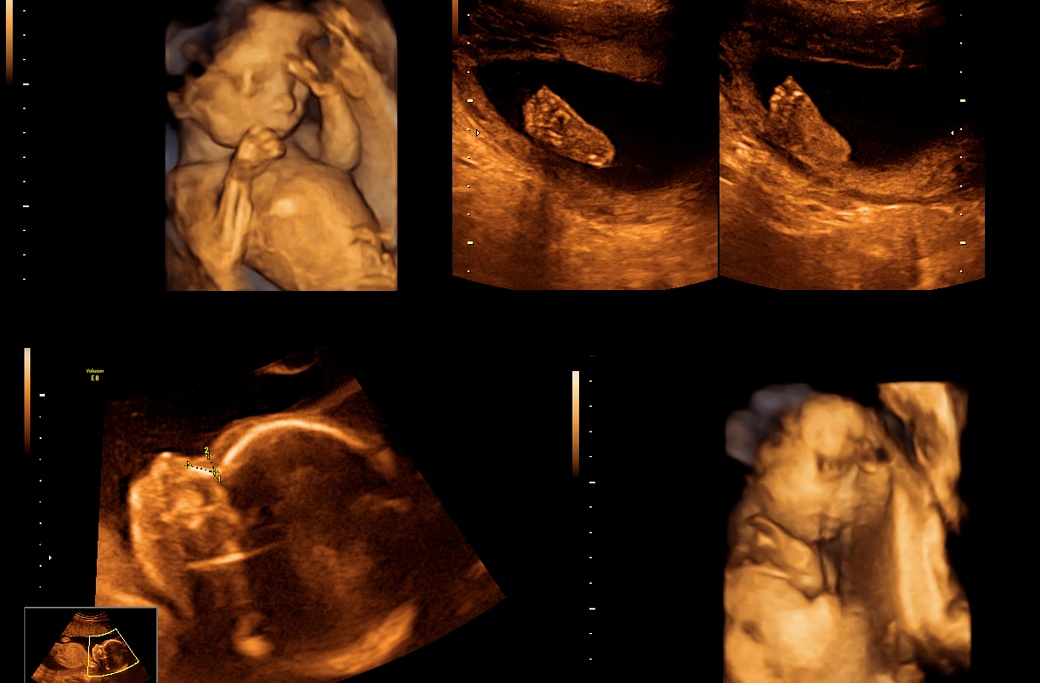

Не предполагали какво предстои да научат. На един от пренаталните прегледи ултразвукът показва нещо изумително. Беата носи в утробата си не едно, а три бебета.

Но и това не било всичко. При по-внимателна проверка се оказа, че само един от ембрионите е имплантиран, което означава, че близнаците са заченати по естествен път. Шокът е голям, изненадата - съвсем неочаквана.

Всички бебета идват на бял свят съвсем здрави. Беата ража Амелия, Матилда и Борис в 34-та г.с., а след няколко дни, прекарани в болницата, всички заедно се прибират у дома.